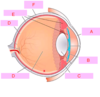

which of the following is attaches to the eyeball posterior to the eyeball equator?

superior rectus

inferior olbique

medial rectus

lateral rectus

superior oblique

what movement does this cause? [1]

which of the following is attaches to the eyeball posterior to the eyeball equator?

superior rectus

inferior olbique

medial rectus

lateral rectus

superior oblique

what movement does this cause? [1]

depression of eye